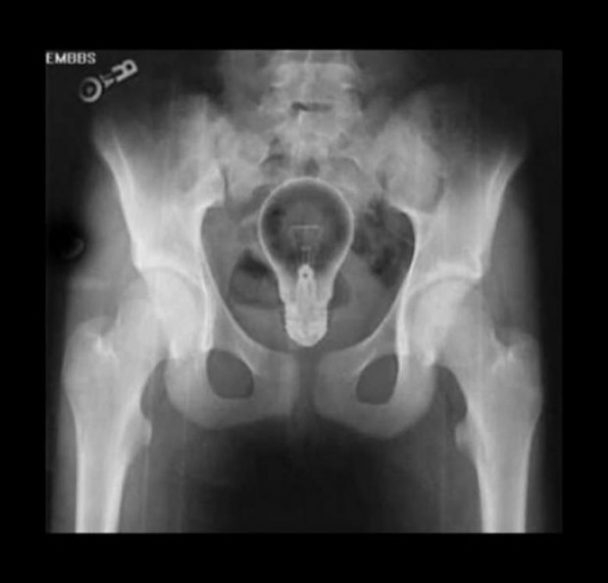

O ŞİŞE ORAYA BAKIN NASIL GİRMİŞ

Röntgen filmlerinden çıkan akıl almaz şeyler

Hastane koridorlarına düşenler bilir… Doktora görün, tahlilleri yaptır, röntgenleri çektir falan filan derken insanın ömründen ömür gider. Gelin görün ki bu sefer çektirilen röntgenlerde öyle ilginç şeyler çıkmış ki ağzımız açık kaldı…